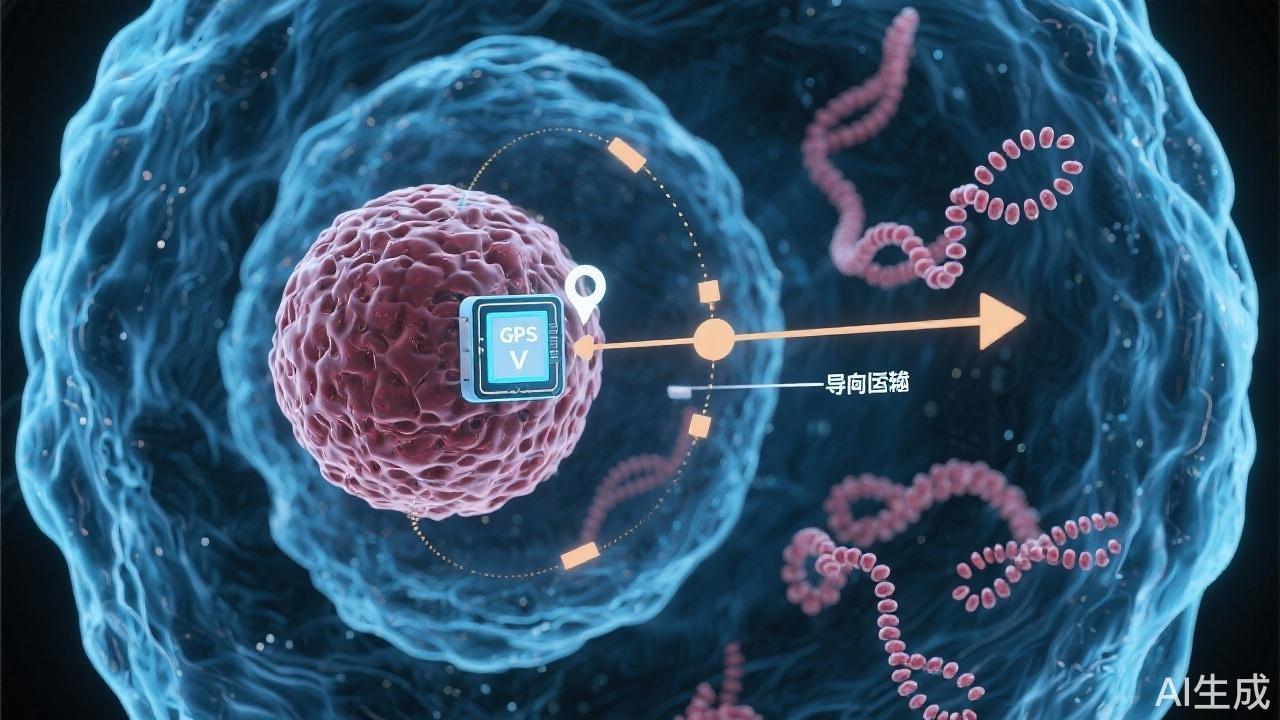

AI模型精準(zhǔn)識別基因與藥物靶點(diǎn)

2025-09-21 01:01:00